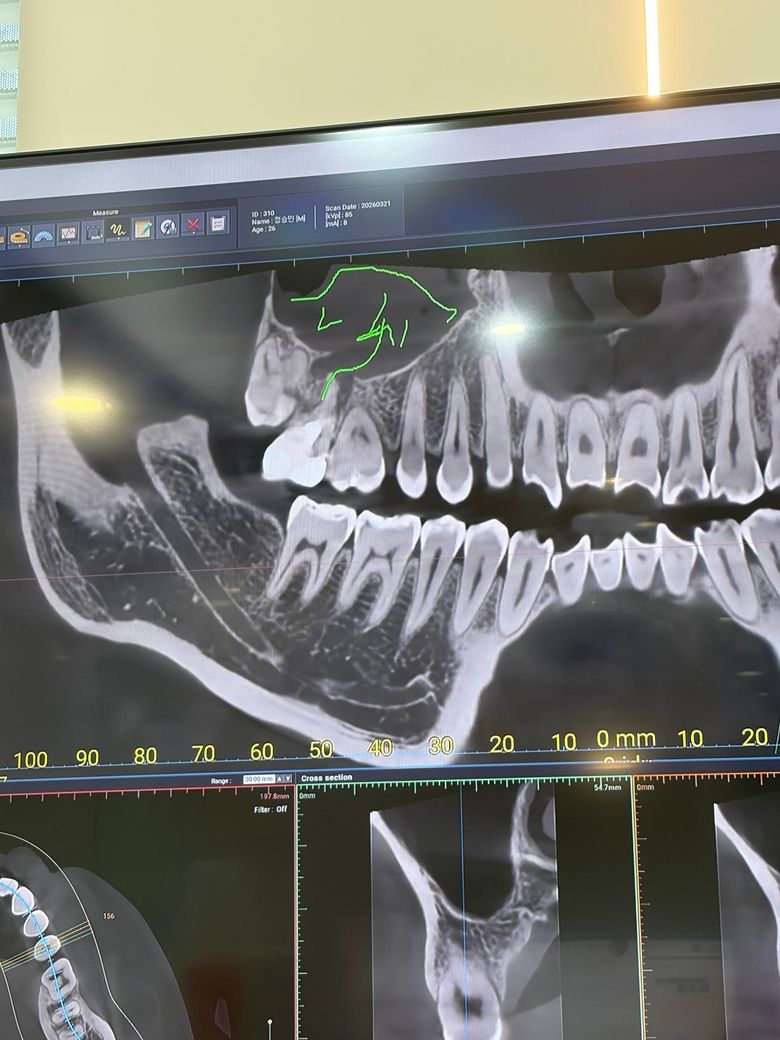

잇몸 뼈가 녹아서 임플란트를 해야한다고 합니다. 해당 치아는 신경치료 했었고, 크라운 씌운지 11년 되었습니다. 통증은 없는 상태인데 검진 받으러 가니까 이미 살릴 수 없고 뽑아야 한다고 하더라구요. 과잉진료는 아닐까요?

염증으로 주변 뼈는 녹고있는 상태입니다 앞으로 얼마나 빠르게 잇몸뼈가 흡수될지는 미지수이나 그대로 두면 계속 잇몸뼈가 녹을겁니다